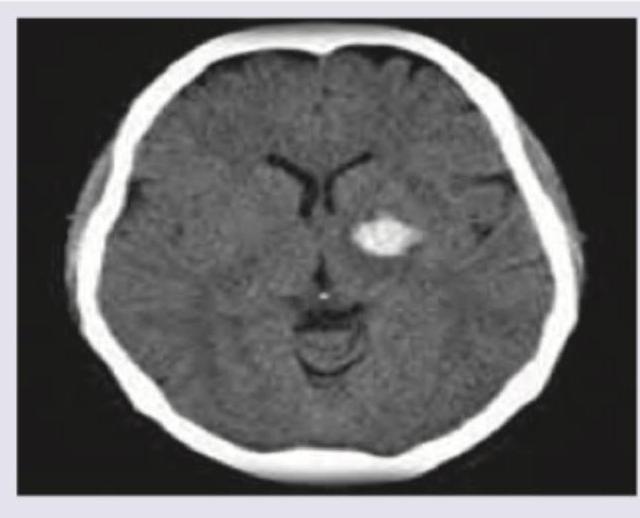

Question 5: A patient presents with GCS of 7 with nuchal rigidity and bloody CSF. Which is incorrect regarding this condition? (Recent NEET Pattern 2016-17)

Explanation: **IV ceftriaxone** - The clinical presentation of **GCS of 7**, **nuchal rigidity**, and **bloody CSF** is highly suggestive of a **subarachnoid hemorrhage (SAH)**, not a bacterial infection like meningitis. - **Ceftriaxone** is an antibiotic commonly used to treat bacterial meningitis, which is not indicated here as the primary issue is hemorrhage, not infection. *Blood in sylvian fissure* - **Blood in the sylvian fissure** is a common finding in **subarachnoid hemorrhage**, as this area contains major cerebral arteries susceptible to aneurysm rupture. - CT scans often show hyperdense (bright) blood within the sulci and cisterns, including the sylvian fissure. *Seizures* - **Seizures** are a relatively common complication of **subarachnoid hemorrhage**, especially in the acute phase due to blood irritating the cerebral cortex. - They can occur in up to 10-20% of SAH patients and are a significant predictor of poorer outcomes. *Intraventricular extension* - **Intraventricular extension** of blood indicates a more severe hemorrhage and is often associated with a worse prognosis in **subarachnoid hemorrhage**. - The presence of blood within the ventricles can lead to **hydrocephalus** and increased intracranial pressure.